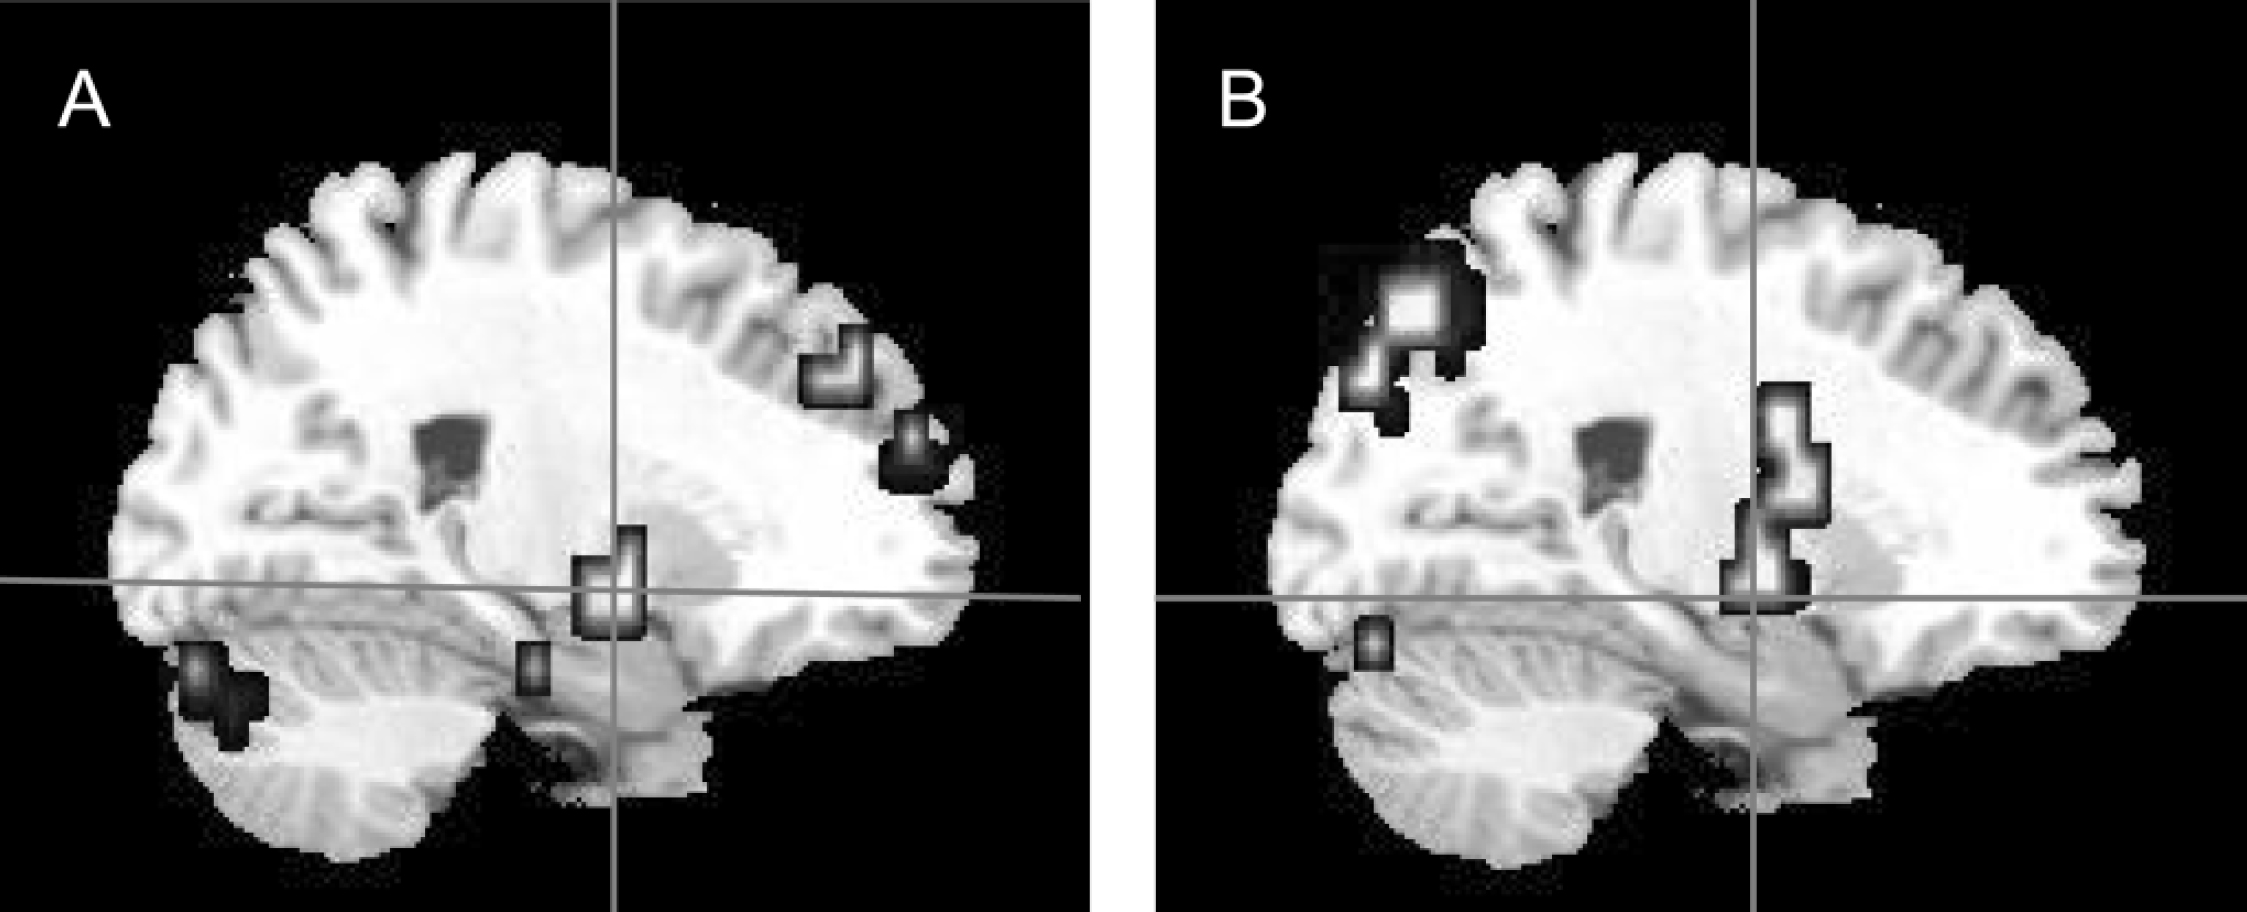

Fig. 2 Sagittal view of the brain showing right amygdala responses to fearful v. neutral faces (a) in the control group (x=25, y=–7, z=–7) and (b) the between-group differences, where control participants demonstrated greater activation than participants with schizophrenia (x=22, y=–7, z=–13).

• Control v. patient groups: activation to fearful faces. Control participants demonstrated significantly greater activation than did the participants with schizophrenia during the processing of fearful faces within the right fusiform gyrus, the left superior temporal gyrus, the bilateral inferior frontal gyri, the right amygdala and right parahippocampal gyrus (Table 2; Figs 1(b), 2(b)).

Correlational analyses in the patient group revealed a significant negative correlation between the PANSS negative sub-scale score and activation within the left superior temporal gyrus during the processing of fearful faces (Pearson r=–0.84, P=0.001; Spearman's rho=–0.74, P=0.01) (Fig. 3). This correlation remained significant after controlling for the patients' IQ (r=–0.805, d.f.=9, P=0.005) and gender (r=–0.847, d.f.=9, P=0.002). No other correlation between measured brain activity and PANSS scores was statistically significant.

Fig. 3 Sagittal view of the brain showing between-group differences in neural response of left superior temporal gyrus to fearful faces, where control participants demonstrated greater responses than participants with schizophrenia (x=–47, y=–22, z=9). The graph shows the correlation between the Positive and Negative Syndrome Scale (PANSS) negative sub-scale scores and the mean blood oxygen level dependent (BOLD) signal change in the left superior temporal gyrus of participants with schizophrenia (Pearson r=–0.84, P=0.001; Spearman's rho=–0.74, P=0.01).